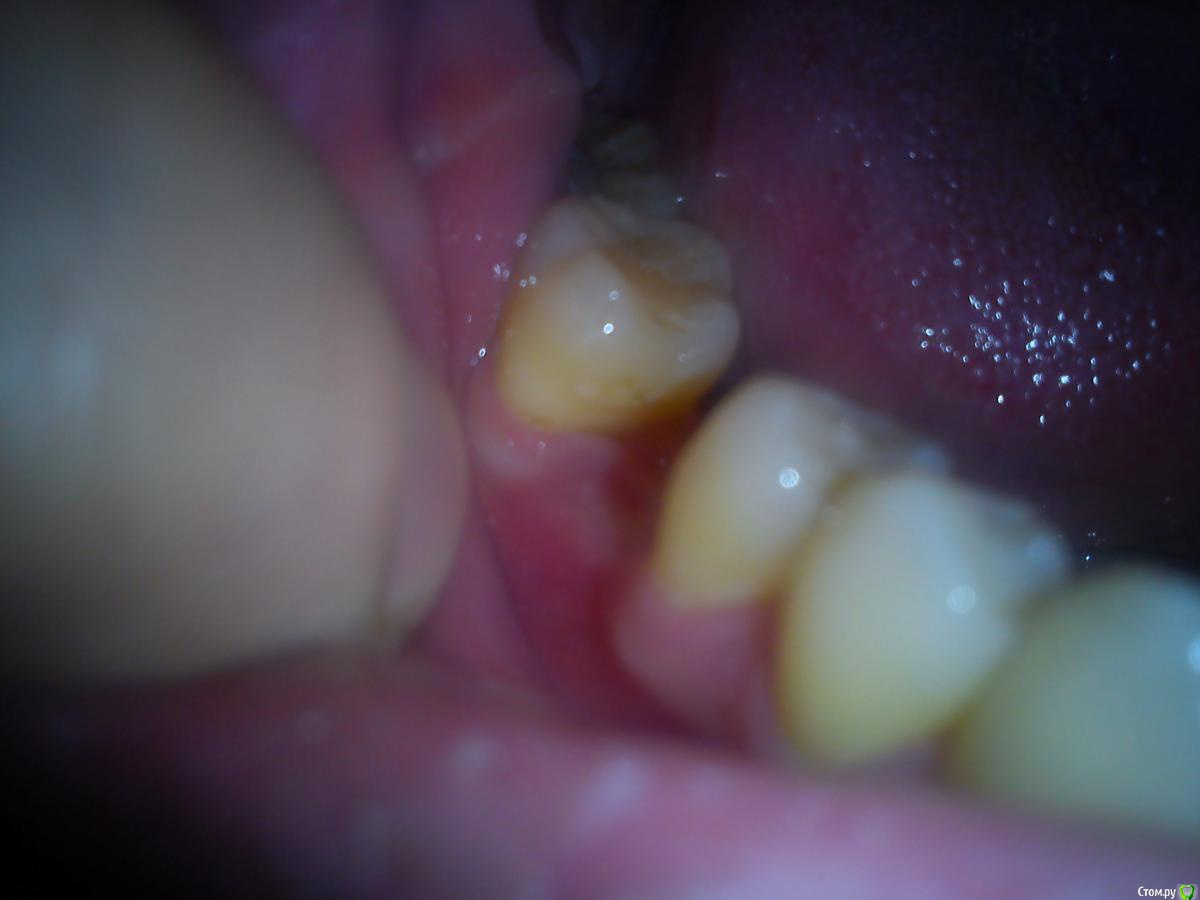

Макс111 Опубликовано 16 декабря, 2015 Поделиться Опубликовано 16 декабря, 2015 Добрый день!По возможности, прошу посмотреть мою КТ. Правда, не разобрался какую именно папку выкладывать, поэтомувот тут ссылка только на папку с файлами с расширением .DCM https://yadi.sk/d/NQrtBNRKmFtRC А вот тут на все содержимое диска вместе с программой для просмотра, на всякий случай:https://yadi.sk/d/O5yoL0QImFu3Y Так же к теме прикрепляю фото 24, 25 с внешней и внутренней стороны, а так же фото ниж ч там где 46 У меня пародонтит, и тд.В целом, вопрос по 24 и 25 зубу, между ними как видно большой карман. 25 это коронка на зубе, десна опустились и она полностью оголилась, видно уже корень , коронка на десной на пару мм. 24 это в общем то пломба огромная на весь зуб.Что можно сделать? Мне предлагают снять коронку, потом сделать лоскутную операцию, в ходе которой подсадить материал для формирования кости, чтоб уменьшить этот карман и потом сделать сделать коронку и на 25 и на 24 тоже коронку одеть.Какое ваше мнение по 24, 25? Как бы вы сделали, в какой очередности?27 и 28 потерял около 9 мес назад, над ними была киста, ее вырезали.А ну и плюс хронический гайморит. Так же прошу посмотреть в низу 46 зуб, можно ли туда вкрутить имплант или предварительно регенерировать кость нужно? каким методом?у 7 ки там такая форма, что между зубами видимо будет пустота? Как с этим бороться? Когда там был зуб так и были и поэтому 46 портился, стояла пломба, но 3 месяца назад он раскололся, сохранить возможности не было, плюс была киста и его пришлось удалить..Стоит ли сразу удалить 48, чтоб он не давил на 47 или можно подождать пока верх сделаю, чтоб было чем есть пока? Спасибо, если кто то посмотрит! Ссылка на комментарий